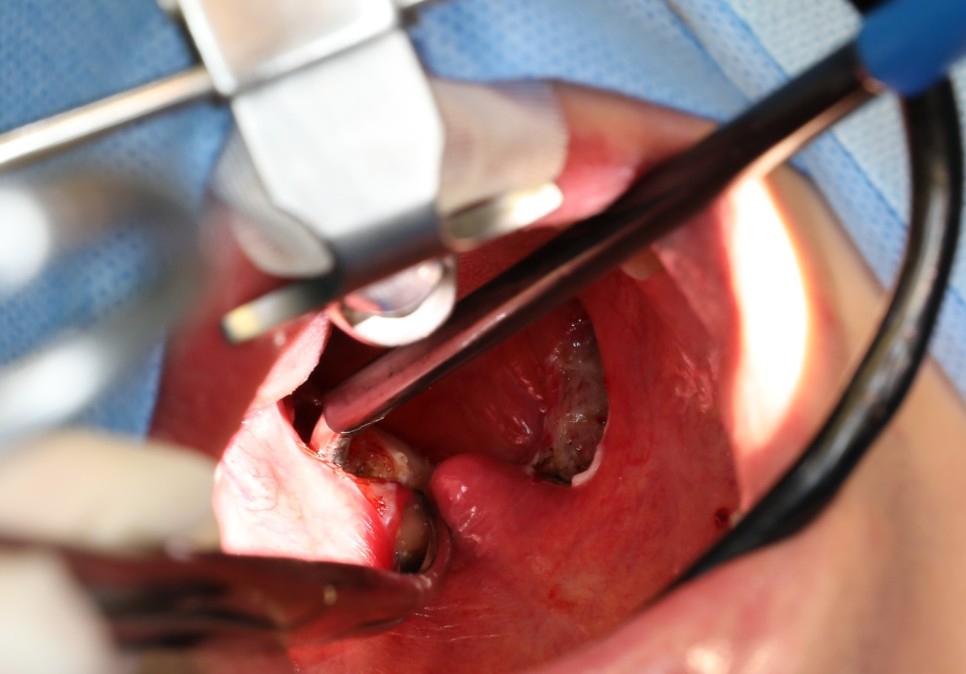

편도를 절제하는 여러 가지 도구가 있습니다. 그 중에서 환자가 선택한 수술 도구는 코브레터였습니다.

편도완전절제술 TOTALTONSILLECTOMY

코브레이션 기술은 고주파 에너지와 식염수를 결합하여 플라즈마장을 생성하는 기술입니다. 플라즈마 필드는 분자를 분해하거나 세포를 태우지 않고 분자 수준에서 편도선을 정밀하게 절제합니다. 접촉 조직에서 상대적으로 낮은 온도(40~70℃)를 유지하기 때문에 주변 조직의 손상을 최소화할 수 있습니다.

이러한 코브레이션 기술은 고압 에너지를 사용함으로써 주변 조직에 손상을 주고 고통을 초래하는 기존 편도선 절제술의 대안으로 개발되었습니다.

편도 결석이 있는 분은 대부분 만성 편도염을 앓는 경우가 많기 때문에 수술 중 출혈이 많지요. 다행히 오늘 환자는 출혈이 많지 않았어요. 대부분 코브레터 편도 절제술은 출혈이 많지 않으면 양측 절제에 15분에서 30분 정도 걸립니다.

수술 중 출혈이 별로 없으면 수술 후 출혈이 심해질 수 있다는 미신이 있으므로 ^^;;보다 꼼꼼하게 지혈작업을 하여 수술을 마칩니다.AFTER 수술 직후▶▶